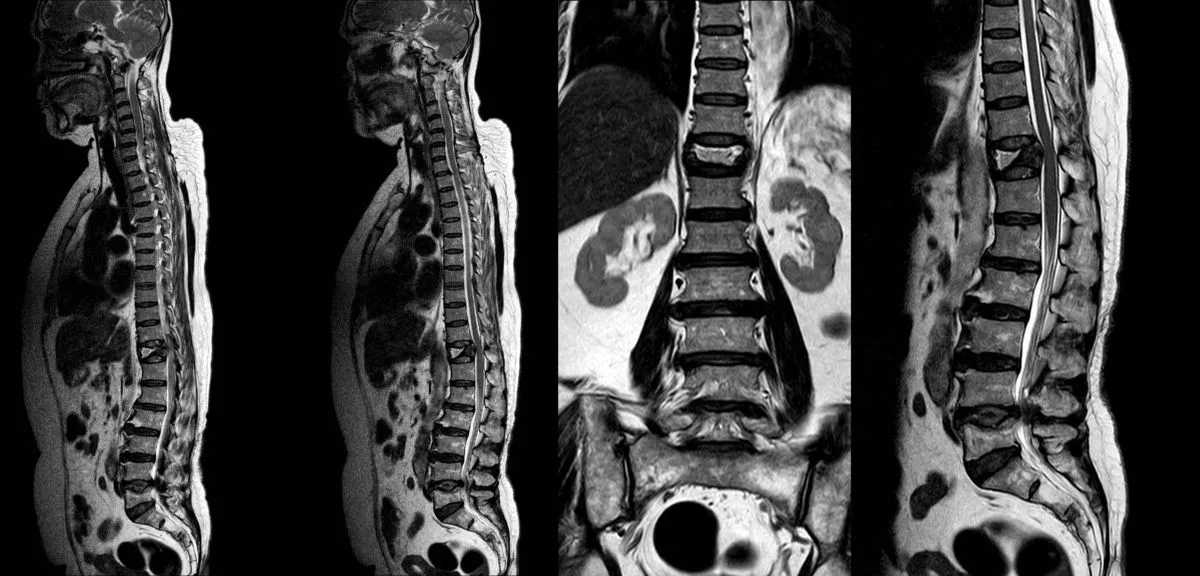

One of the most critical aspects of addressing spine health in menopausal women is ensuring accurate diagnosis. This requires more than just imaging studies; it demands a comprehensive evaluation that correlates your symptoms with physical examination findings and imaging results.

Too often, patients receive diagnoses based solely on MRI findings without proper clinical correlation. An MRI might show disc degeneration, a bulge, or osteoarthritic changes, but here’s the crucial point: these findings are extremely common in people without any pain. The presence of an abnormality on imaging doesn’t automatically mean it’s causing your symptoms.

A proper diagnostic approach requires three components working together:

- Detailed clinical history: When did symptoms start? What makes them better or worse? How have they progressed?

- Comprehensive physical examination: Neurological testing, range of motion assessment, palpation, provocative tests

- Appropriate imaging: MRI for soft tissue evaluation, DEXA scan for bone density, X-rays for alignment and structural assessment

Only when all three components align can your physician confidently identify the specific pain generators, the actual structures causing your symptoms. This is especially important for menopausal women who may have multiple overlapping conditions: osteoporosis with vertebral fractures, disc degeneration causing discogenic pain, facet joint arthritis, and spinal stenosis can all coexist. Each requires different treatment approaches.